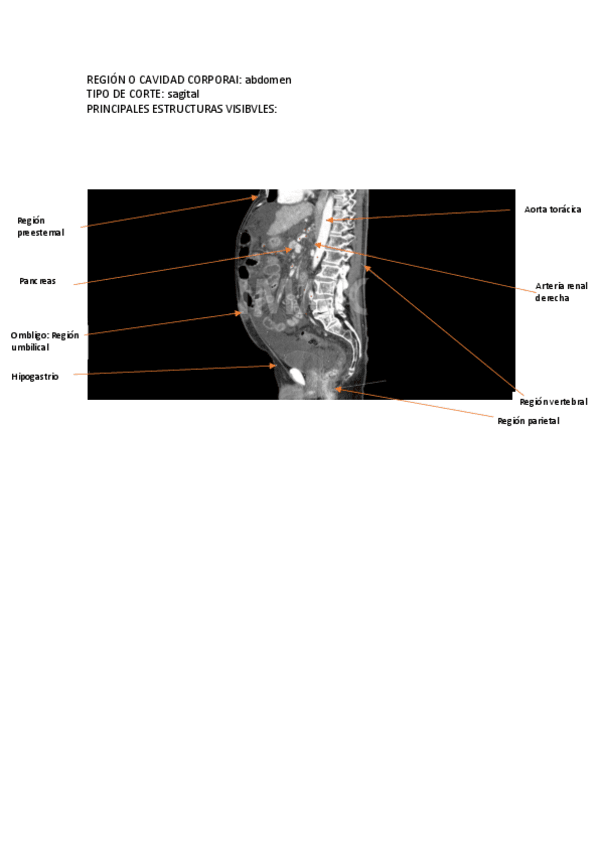

Sagital-abdomen.pdf